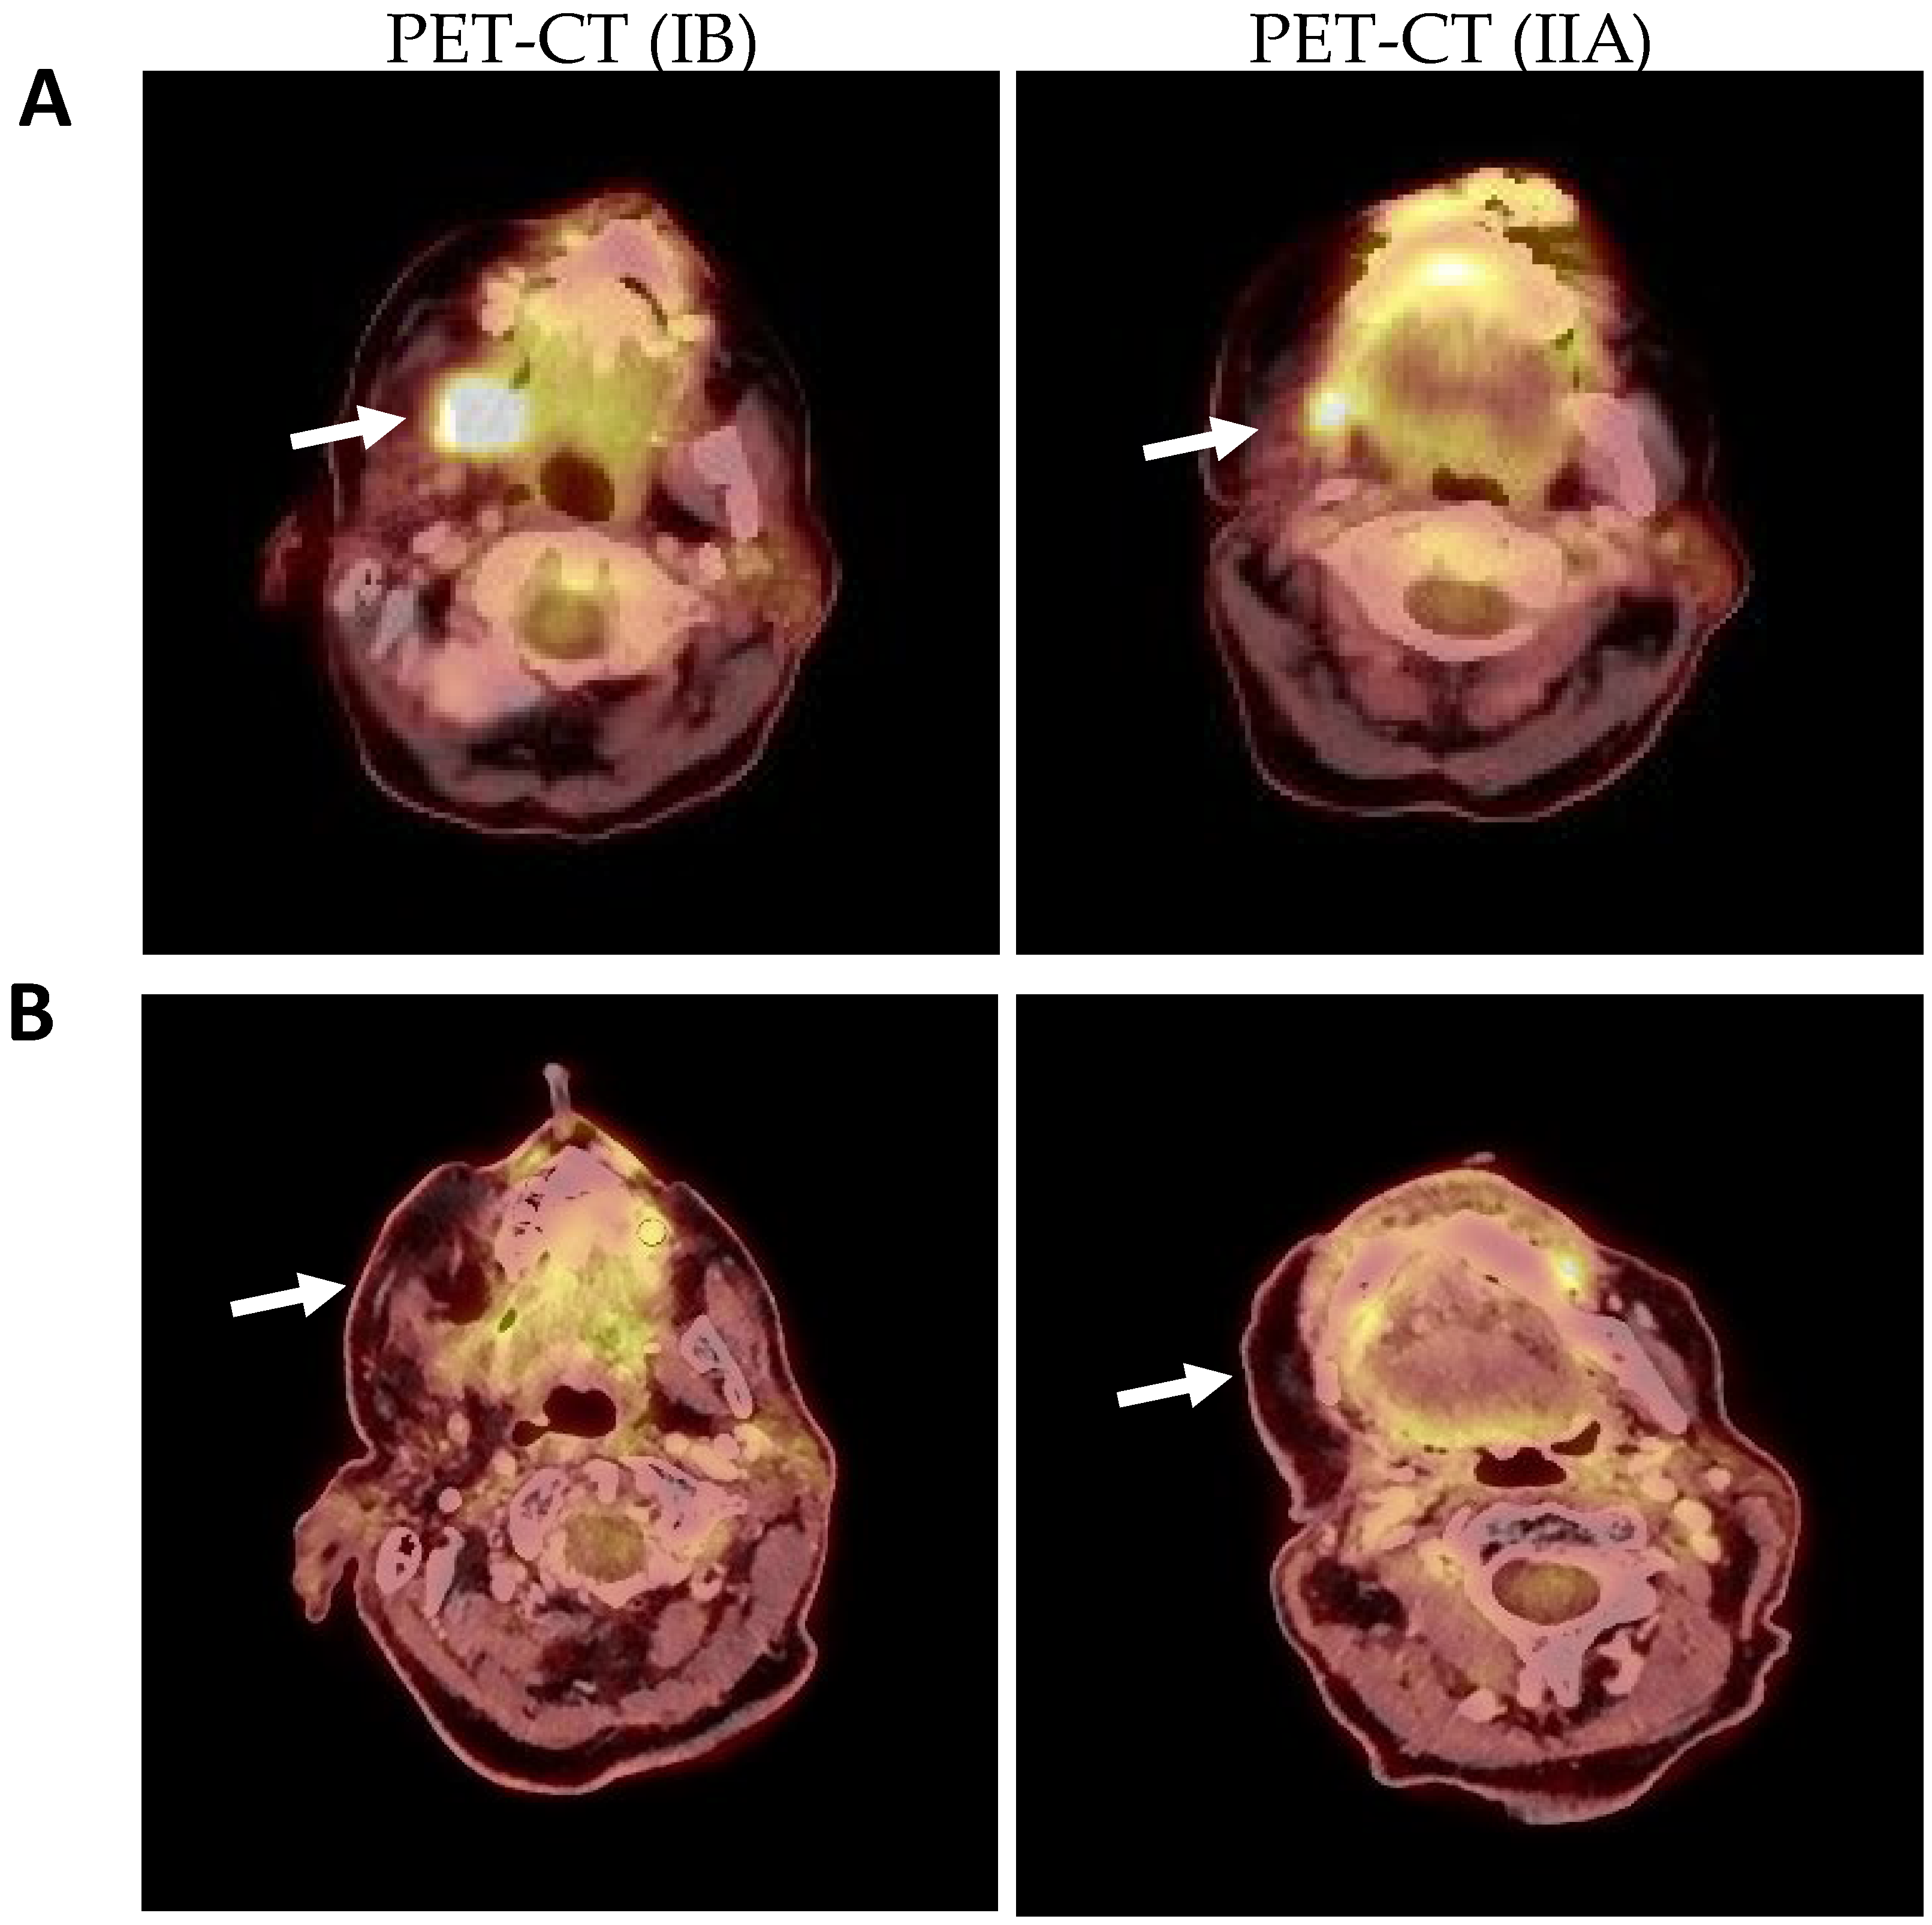

2. Results

2.1. Clinical and Histological Manifestations of the Tumors

4.3. Positron Emission Tomography-Computed Tomography